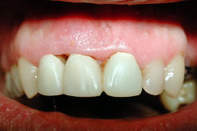

Tehnicile adezive directe de lucru cu materiale bazate pe rasini composite reprezinta o modalitate excelenta de restaurare estetica si minim invaziva a dintilor frontali. Obtinerea rezultatelor estetice asteptate este legata indesolubil de alegerea si utilizarea corecta, conform indicatiilor, a materialelor si tehnicilor de lucru adecvate, fiecarei situatii clinice.